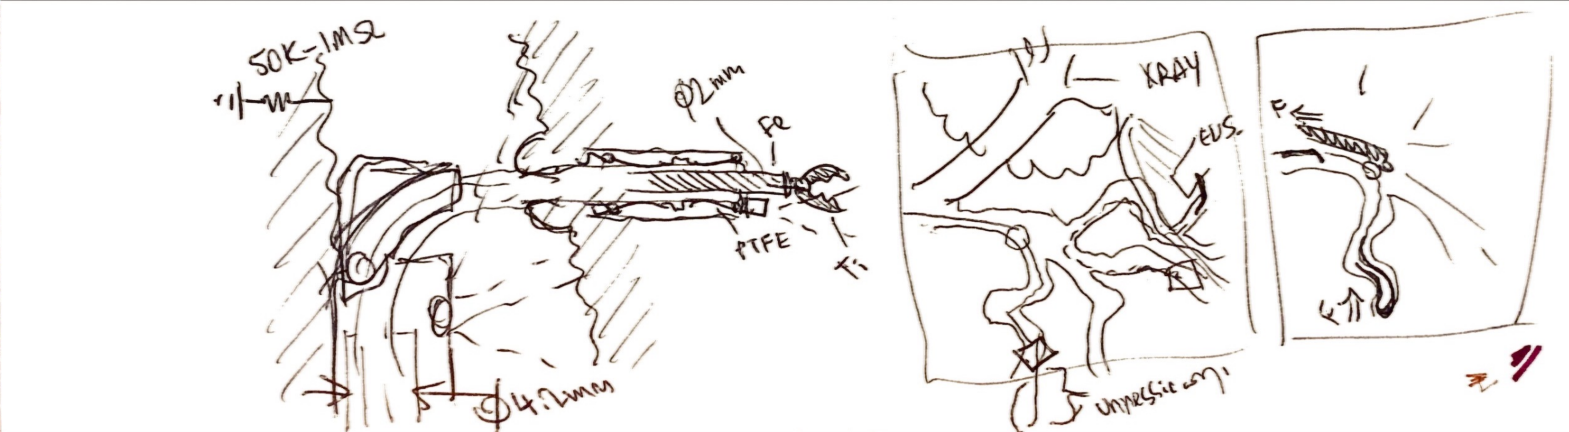

Working alongside Dr. Todd Baron and Dr. Lisa Gangarosa at UNC Hospital's Advanced Endoscopy Fellowship, our team identified a clinical need: existing endoscopic tools create post-surgical complications that a redesigned actuator geometry could reduce. I led a team of eight through three years of design, prototyping, and verification — beginning with OR shadowing to understand the procedure environment firsthand.

The design process ran from clinical needs-statement development through ideation sketches — specifying PTFE sleeves, titanium construction, ø2mm working channel geometry, and shape-memory alloy actuation rings — to full parametric CAD and a working proof-of-concept prototype with embedded electronics and an OLED UI displaying power level, machine history, and current position.